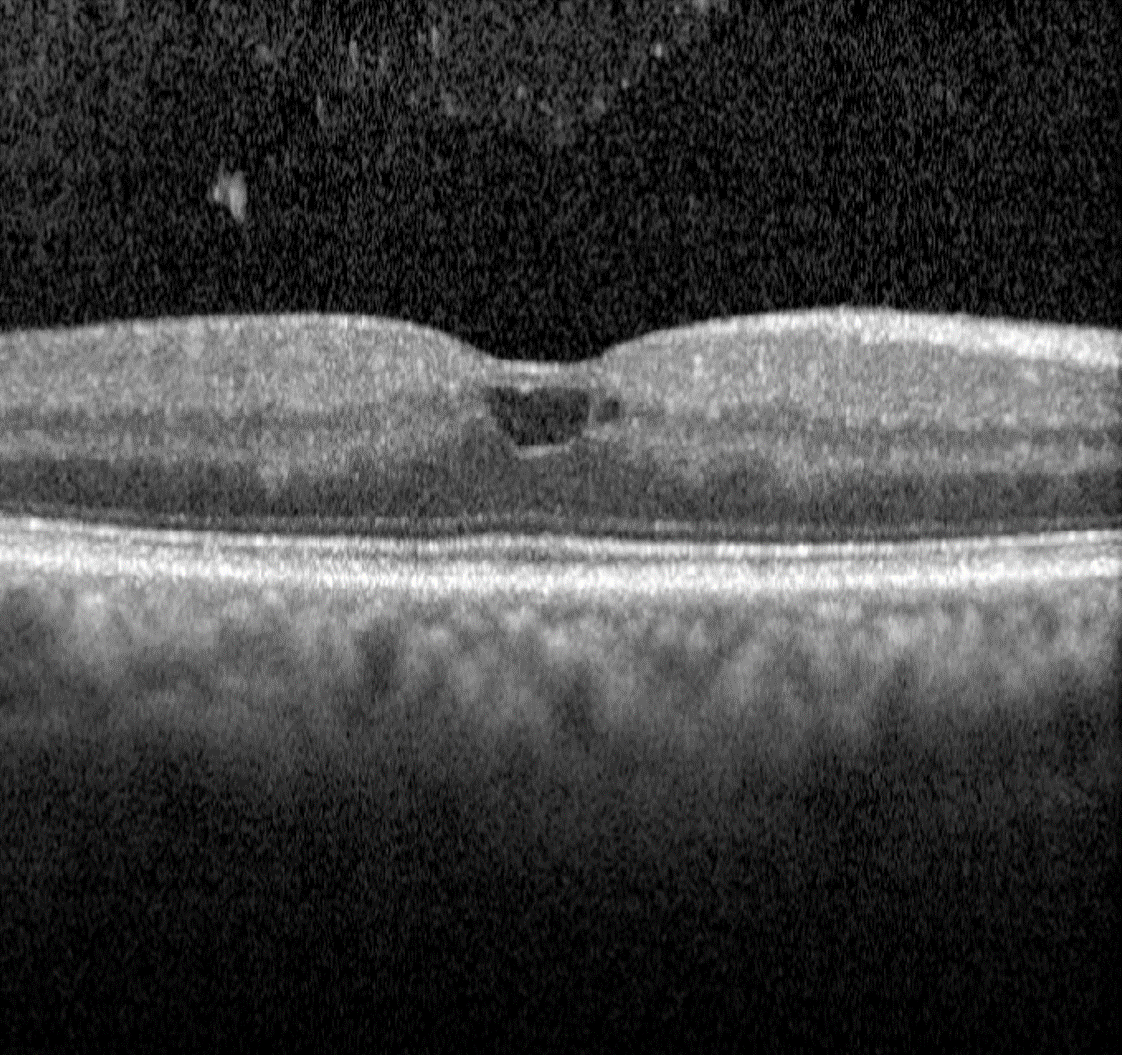

Clinically, they appear as isolated, round red dots of varying size which can resolve spontaneously. They may be undetectable on OCT or, if visible, typically appear as small round or oval lesions, originating from either the superficial or deep capillary plexi , fully or partially capsulated in 56% of cases.

On OCT angiography they may be seen as a small area of hyper-reflectivity adjacent to a blood vessel within the inner retinal layers.

Fundus photo, red-free image, OCT line scan, OCT angiography - Microaneurysm